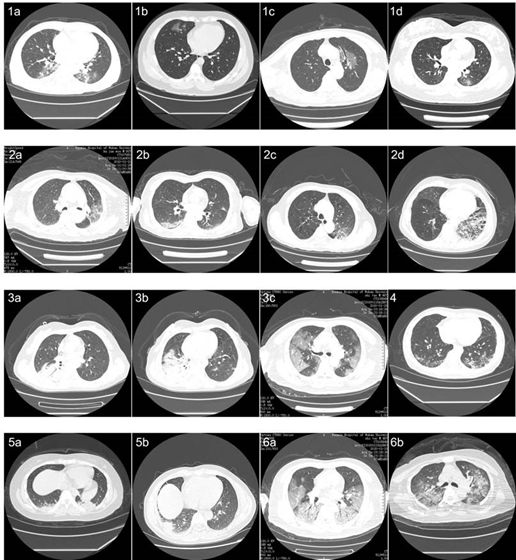

如图1所示,共收集51例COVID-19肺炎患者和55例其他疾病对照患者的46,096张CT扫描图像,用于建立COVID-19肺炎的模型。在过滤了那些没有良好肺炎的图像后,选择了35355张图像,并将其分成训练和回顾性测试数据集。在训练数据集中登记的图像几乎涵盖COVID19肺炎的所有常见CT特征,如图2所示。3名具有5年以上临床经验的放射科医师在训练数据集中标记COVID19肺炎患者的感染病症,在检测集中选取包含COVID19肺炎病灶的影像,并将其标记进行一致合并。为了对模型进行前瞻性测试,进一步收集了2020年2月5日在武汉大学人民医院连续接受CT扫描的27名患者的13911张图像。所有CT扫描均在武汉大学人民医院进行。本研究使用的仪器包括Optima CT680, Revolution CT和Bright Speed CT扫描仪(全GE医疗)。

图4 模型预测的代表性图像。A. COVID19肺炎的CT图像。人工智能模型和放射学家的预测是一致的。绿色方框,放射科医生的标签; 红色的盒子,模型的标签。B.对照组CT图像。第一张是普通细菌性肺炎,显示右下肺叶实变。第二张图片为肺部肿瘤病变,左上肺叶有肿块,边缘有毛刺,叶状生长,内部有液泡。第三张图片是继发性肺结核,显示左侧根尖纤维束。第四张图片为支气管扩张合并感染,表现为支气管扩张、扩张、囊性改变及周围感染斑块。第五张图显示的是正常的肺。